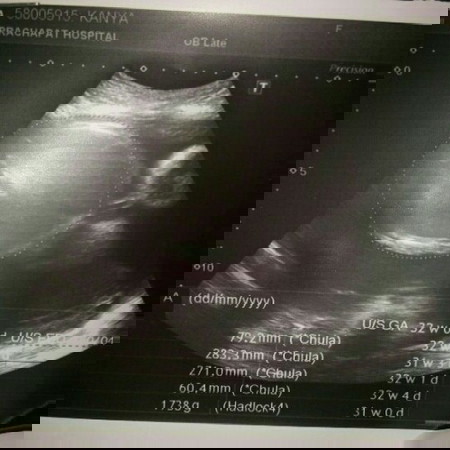

อยากรุ้ค่ะว่าลูกกี่Wแล้ว แล้วตัวเล้กมั้ยพอดีไปฝากตอนท้องเริ่มใหญ่เหมือนคนกินพึ่งอิ่มค่ะ หมอบอก8เดือนแต่ท้องเล้กมากค่ะ อยากรุ้ว่าเด็กจะปกติมั้ย